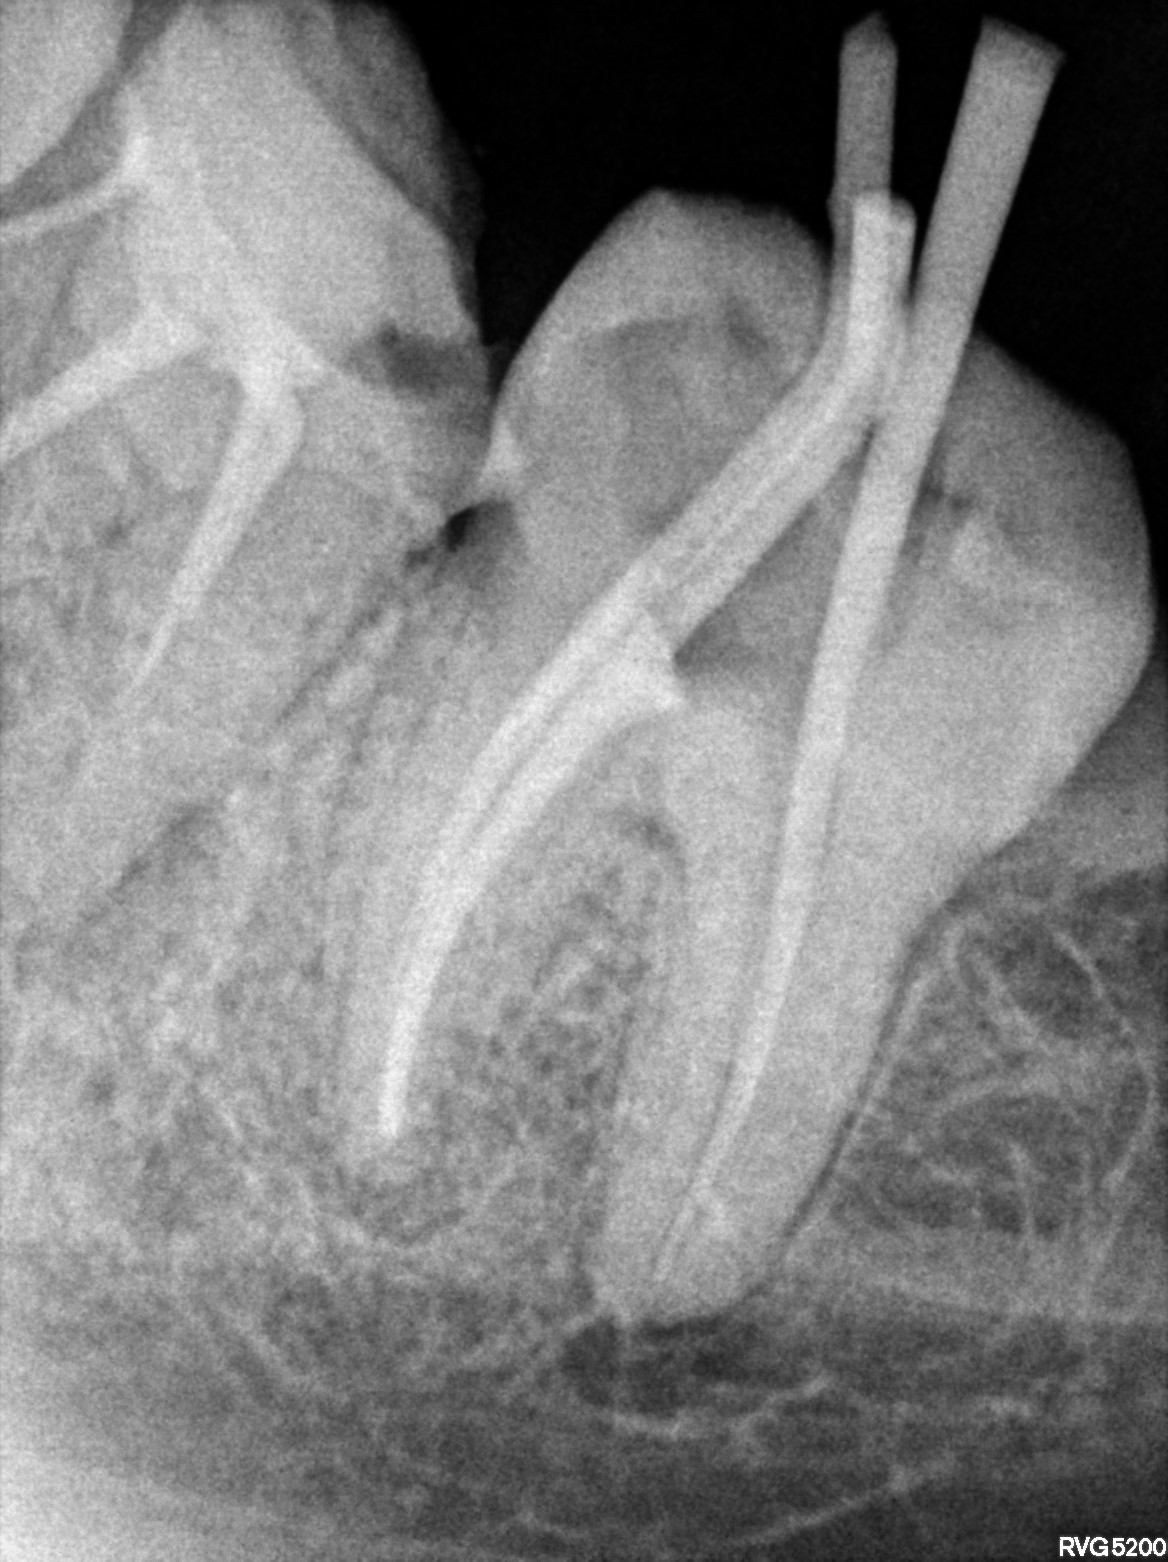

Dental Radiographs FHIR: DocumentReference · LOINC 24641-7

xray_1758897542_0.jpg

24641-7

| Root canal treatment | 234780006 | D3330 Endodontic therapy, molar tooth | ##37 | 2026-02-23 | completed | A/o 37, distal 25.06 till apex WL 2 stopper, mesial canal 20.04 arbitrary WL 2 stopper | |

| 2026-02-23 22:13 | fulfilled | A/o 37, distal 25.06 till apex WL 2 stopper, mesial canal 20.04 arbitrary WL 2 stopper — Dr Riyaz | |